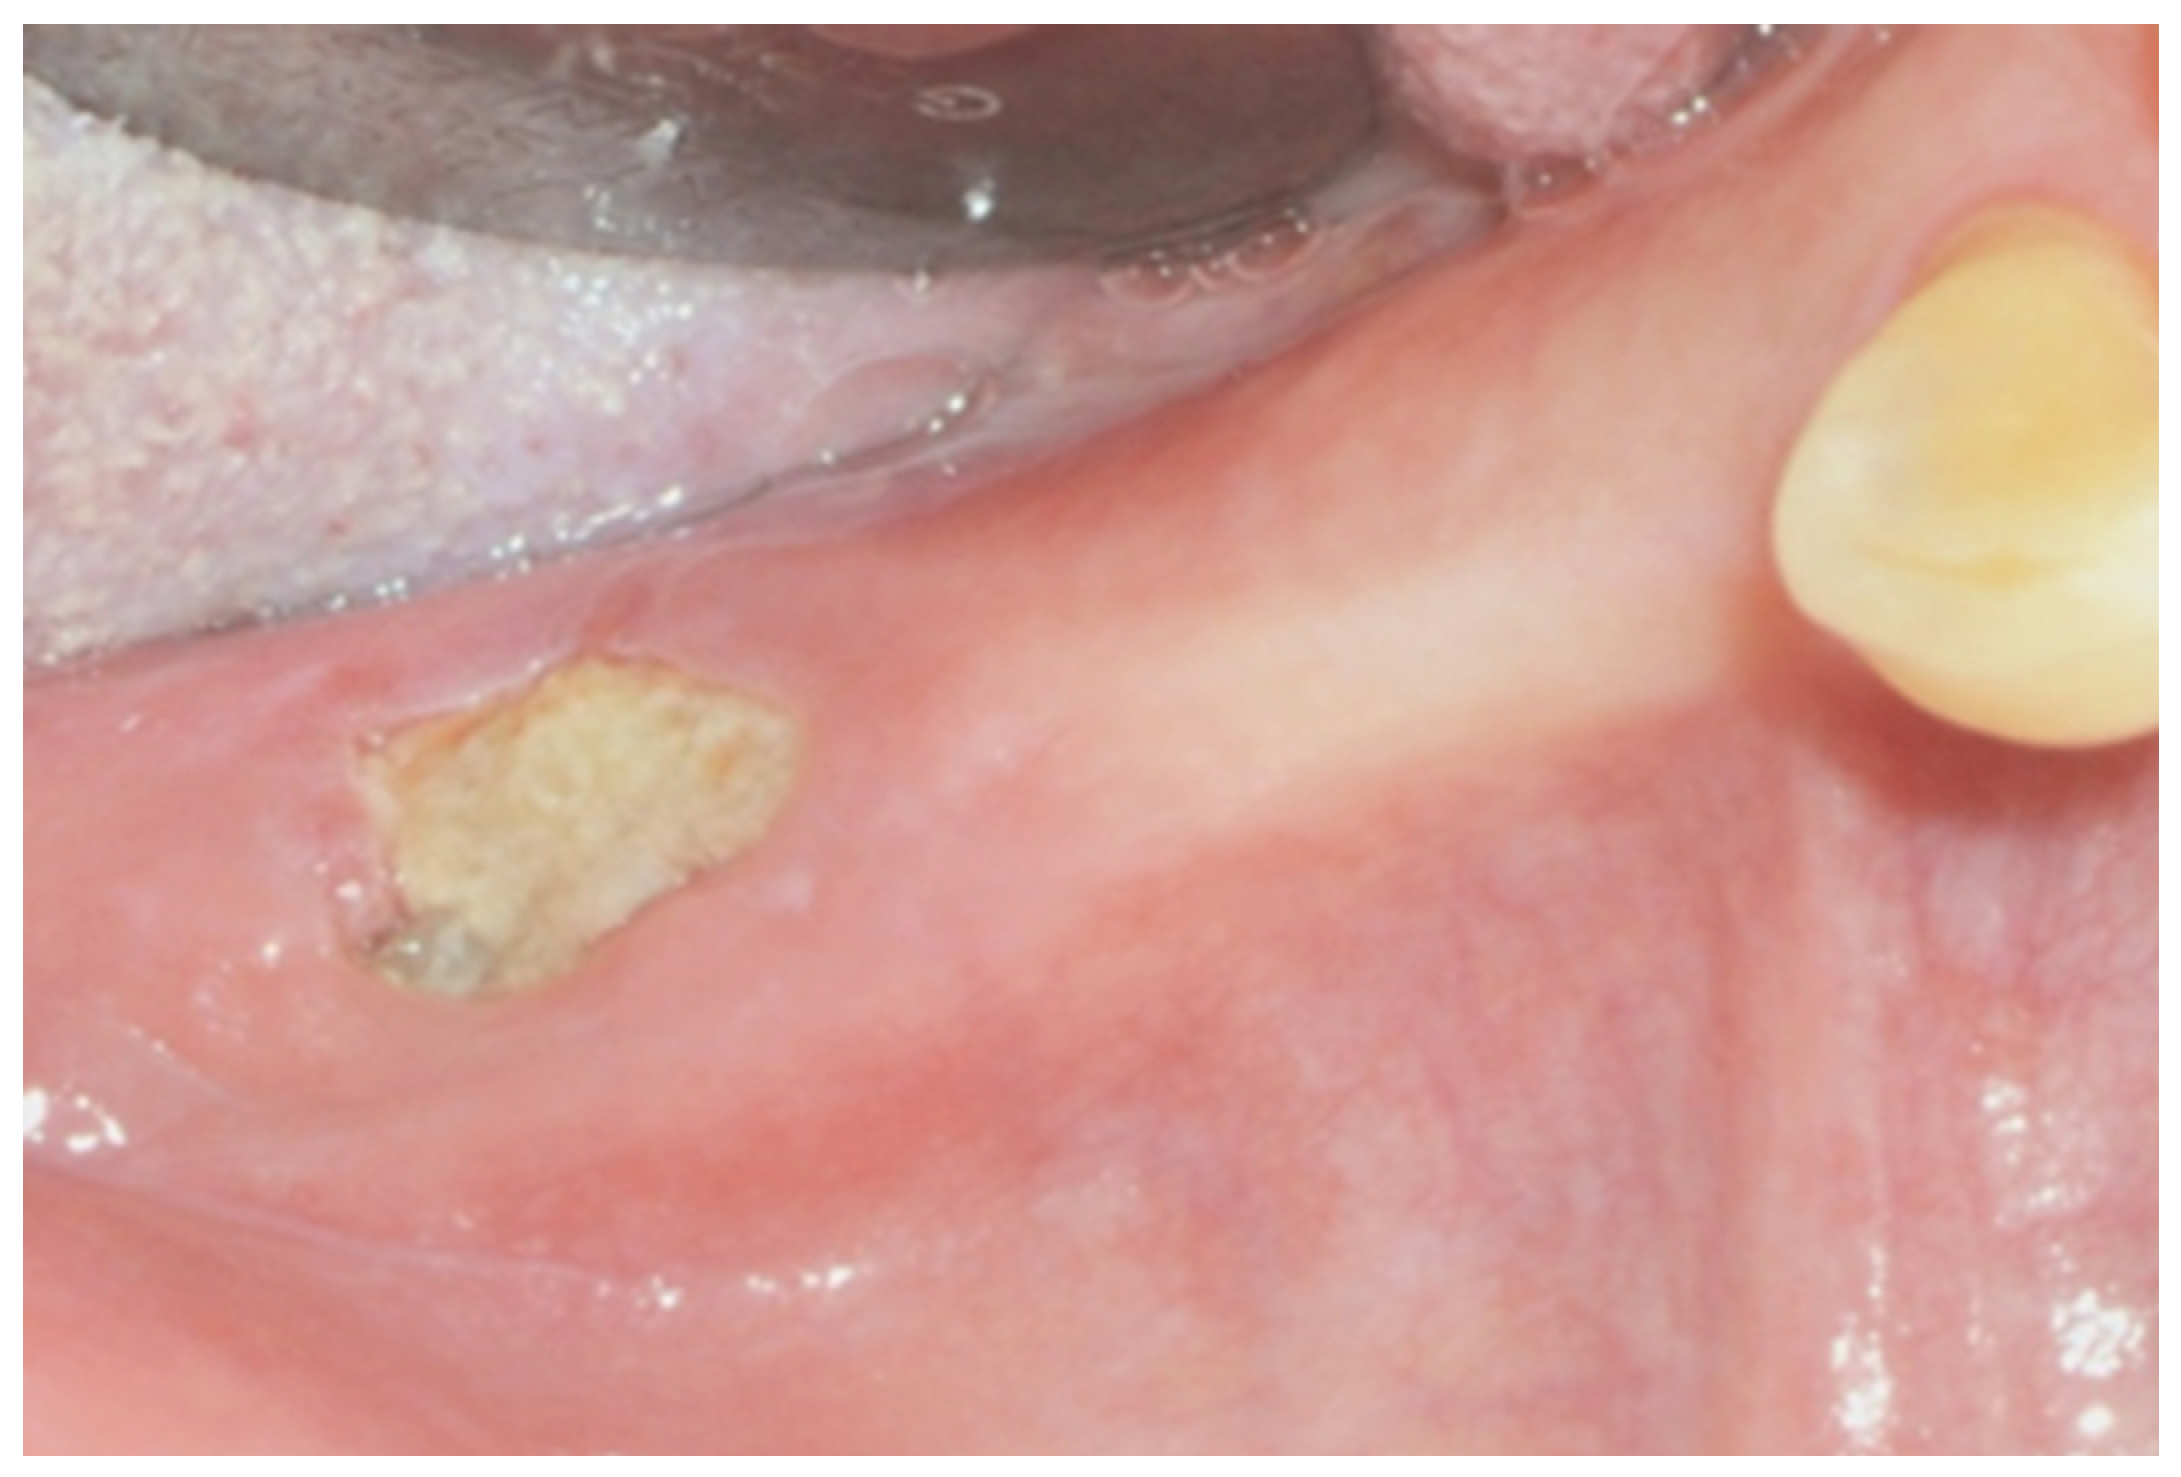

| Patient | Age | MRONJ Stage |

|---|---|---|

| Patient 1 | 44 | I |

| Patient 2 | 79 | II |

| Patient 3 | 61 | II |

| Patient 4 | 69 | I |

| Patient 5 | 85 | III |

| Patient 6 | 77 | I |

| Patient 7 | 65 | I |